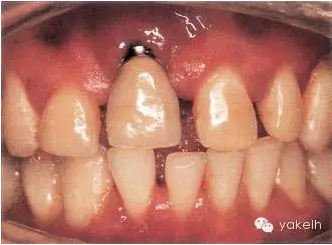

病例6

這個(gè)病例展現(xiàn)的錯(cuò)誤比較典型,臨床醫(yī)生在種植體植入過程中,位置選擇不正確。該病例UR2準(zhǔn)備行種植修復(fù)。然而由于軟組織缺損,種植體肩臺(tái)(邊緣)暴露。同時(shí)種植體植入過深(圖.9A),方向過分偏于唇側(cè)(圖.9B)。種植體植入位置不理想,不可避免地會(huì)導(dǎo)致美學(xué)失敗。

圖.9 種植體植入過深以及太過唇側(cè),最終導(dǎo)致美學(xué)問題。